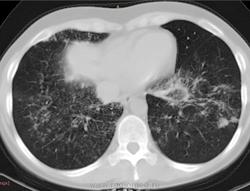

38 лет. 6 лет назад cr носоглотки. Лучевая и химиотерапия. С июля 2012 г. клиника бронхолегочного заболевания.

Флюорография 2010 - норма. В анамнезе хронический гайморит. Бронхоскопия- признаки неспецифического эндобронхита. Исходная флюорография на бумажном носителе с низким качеством изображения. Описаны тени в верхушках легких, воспалительные изменения в средней доле. Лечение макролидами амбулатороно  дало кратковременный эффект.

Узелки хаотичного распределения (туб, микозы, мтс). Участки, напоминающие дерево-в-почках. На верхушках посттуберкулезный фиброз, при этом верхние отделы, насколько можно судить, чистые. Прикорневой фиброз и тракционные бронхоэктазы нижних отделов. Преобладание процесса в нижних долях + фиброзные изменения, +  утолщение??? междолькового интерстиция. Значимой лимфаденопатии не нашла, выпота тоже.

На первое место - неспецифическая интерстициальная пневмония. Спецпневмофиброз верхушек. Насколько возможна реактивация туберкулеза прогнозировать не берусь.

Присоединюсь к ЛГ (со всеми ее оговорками): ДИЗЛ, неспецифическая интерстициальная пневония, участки фиброза, бронхиолита.

Хотелось бы увидеть КТ в другом окне. По-моему, за онко ничего нет, больше всего склоняюсь к саркоидозу. Обширность поражения от верхушек к куполам. Да и участки фиброза в верхушках видел неоднократно, писали , что ТБЦ, а оказывалось саркоидозом. Единственно, смущают бронхоэктазы.